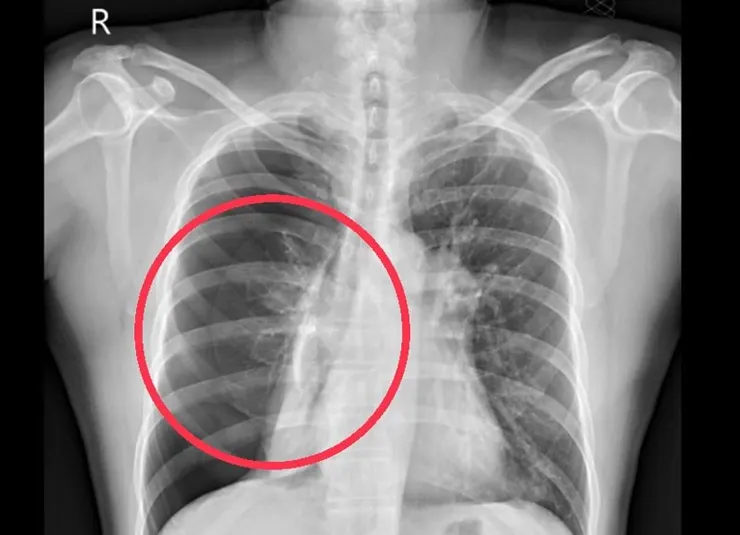

高三那年,我因為從小到大過度累積情緒與悲傷壓力,引發了第一次的自發性氣胸。進了醫院做肺葉切除手術,左肺開刀少了五分之一,出手術室開始插管治療的那時候,正逢高中要上大學的時段。我放棄了大學聯考,改成推甄上榜。依稀記得手術室推出來還插著管的我,肋骨間大拇指大的引流管湧出的血水,一個翻身都痛到全身冒汗,還能在這樣的情況下把推甄的文件都準備完。如同癱瘓一樣的在病床上,敲擊筆電鍵盤疾筆振書。

出院後推甄面試的日期來到,未拆線的傷口、厚厚的紗布,面試學校陡峭的山路讓我滲出的血水,不斷浸濕擴染蒼白的襯衫。我不知道沒上是因為我沒化妝的臉太慘白,還是襯衫的鮮紅嚇到了教授。